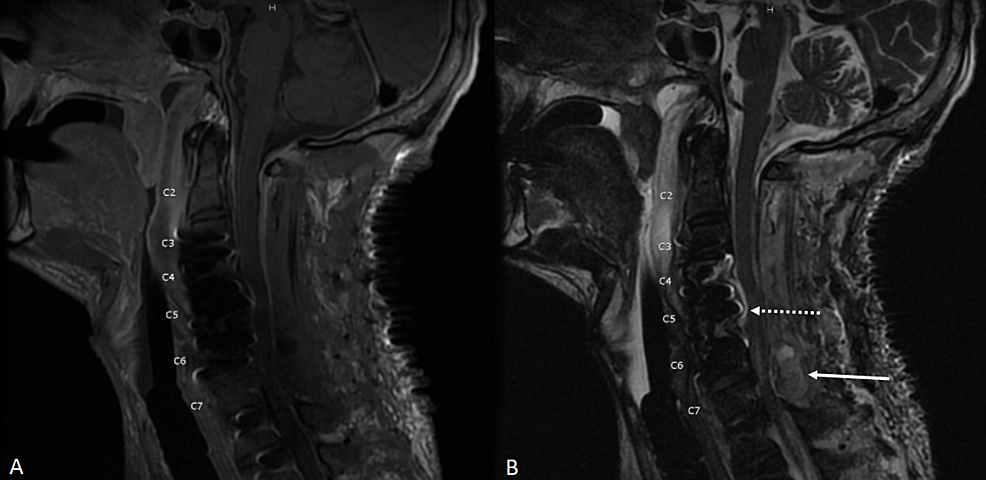

Spinal fusion is surgery to join two or more vertebrae into one single structure. Metal screws that stabilize the spine may move or break before the bones are. Spinal infections are rare, but, when they happen, they can be destructive if not treated promptly and properly.